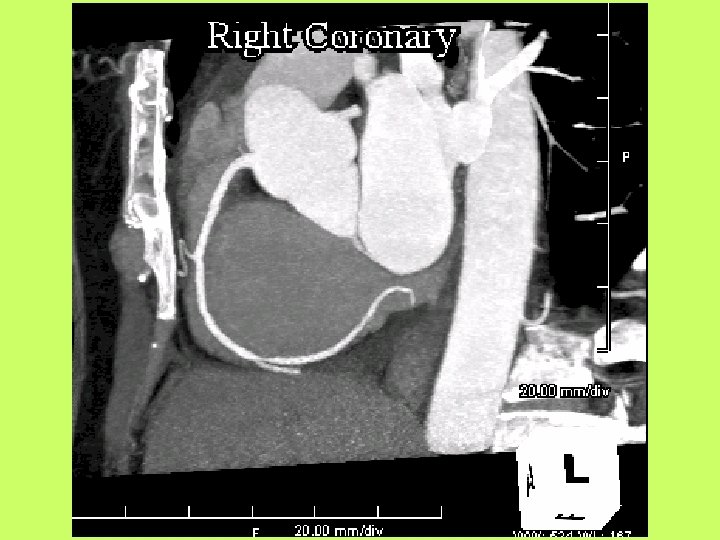

Noninvasive cardiac diagnostic studies 1 - EKG 2 -Chest X ray 3 -Exercise tolerance

Noninvasive cardiac diagnostic studies 1 - EKG 2 -Chest X ray 3 -Exercise tolerance test(ETT) 4 -Echocardiography transthoracic-trans esophagial 5 -Stress echocardiography 5 -Radionuclid imaging 6 -Cardiac catheterization